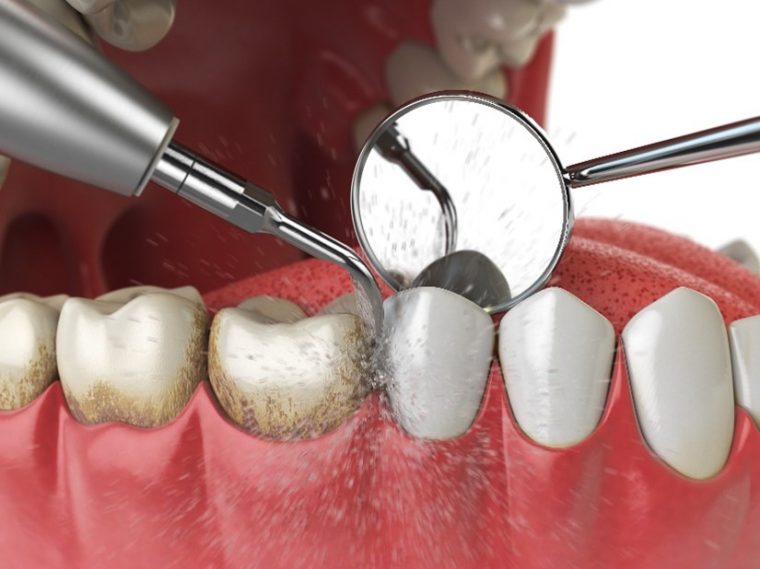

超音波の振動で汚れを落とすイメージイラスト

歯科クリニックで受けるプロフェッショナルケアでは、プラークと歯石を徹底的に除去します。

歯石やプラークは、歯ぐきより上の部分についているものと、歯ぐきより下の歯周ポケットの奥深くについているものがあります。

歯ぐきより下についている歯石は硬く、歯にがっちりとついているのが特徴です。その歯石を取らなければ、さらにプラークが付着して、歯周病が悪化します。

歯科医院の歯のクリーニング専用の機械で歯を磨かれている様子

毎日のセルフケアでは、落としきれない部分をしっかり除去すると、歯ぐきの状態が改善されます。歯石とプラークを除去し、研磨すると歯面はツルツルの状態になり、プラークがつきにくくなります。